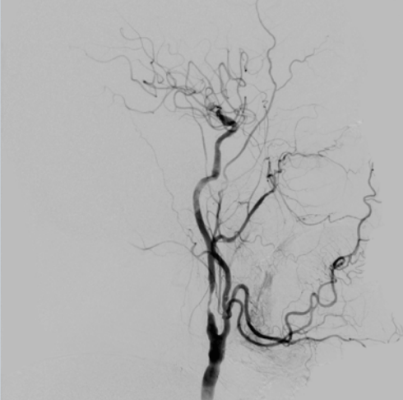

La 28 mai 2014, în sala de operaţii Hybrid a SCR, a fost realizată prima investigaţie invazivă de angiografie tridimensională rotatorie la un pacient cu ictus ischemic suportat. Rezultatele obţinute în cadrul acestei proceduri au influenţat decisiv etapele de tratament chirurgical planificate.

Pacientul investigat, un bărbat de 62 ani, a suportat un accident vascular cerebral cu o lună înainte de adresare, iar în urma accidentului a fost supus unei intervenţii chirurgicale de dezobliterare a arterei carotide din dreapta. În perioada postoperatorie, a fost înregistrată o ameliorare substanţială a stării neurologice, iar pacientul a fost planificat pentru a două etapă a tratamentului chirurgical. Pentru a lua decizia referitor la volumul şi tipul operaţiei asupra vasului arterial controlateral, a fost nevoie de o investigaţie ultraperformantă, angiografia rotatorie tridimensională, care a fost realizată în sala de operaţii Hybrid a SCR.

Sala de operaţii Hybrid a SCR a fost concepută ca şi facilitate diagnostică şi de tratament pentru pacienţii neurochirurgicali. De aceea, instalaţia de Angio-CT din această sală este dotată cu toate opţiunile disponibile pentru investigaţia creierului, vaselor magistrale ale creierului şi măduvei spinării. Una dintre posibilităţile remarcabile ale echipamentului este capacitatea de a investiga şi a calcula volumul de sânge circulant prin orice porţiune a creierului (PBV) sau aşa-numita ”perfuzie cerebrală”, ceea ce este deosebit de important pentru pacienţii cu accidente vasculare cerebrale suportate.

Procedura diagnostică a decurs fără complicaţii, iar pacientul a fost externat a doua zi, în stare satisfăcătoare, după o perioadă de monitorizare de 24 ore.

Realizarea investigaţiei a fost posibilă în cooperare cu secţia de chirurgie endovasculară a SCR şi a unui expert al companiei Siemens, producătorul instalaţiei ”Artis Zee”. Întreaga echipă de neurochirurgi, condusă de Dr. Aurel Bodiu şi chirurgie endovasculară, condusă de Dr. Eduard Bernaz a realizat anterior un curs de perfecţionare de 2 săptămâni direcţionat spre însuşirea posibilităţilor multiple ale echipamentului.